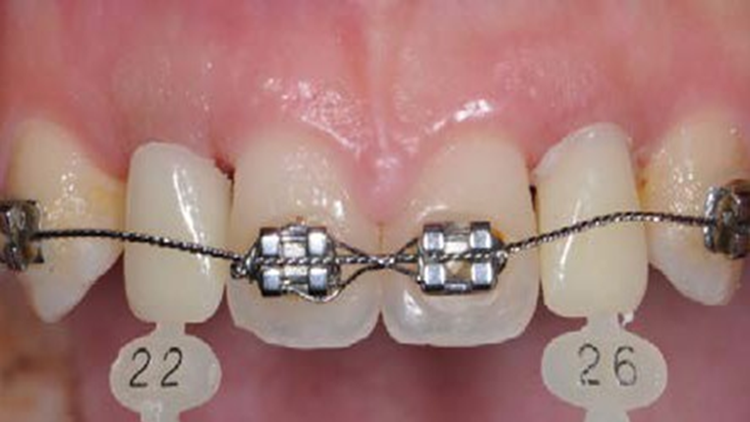

Clinical case: Patient-centered approach: treatment strategy for Root Membrane Technique & delayed implant placement

- Courtesy of Dr. Yoshiharu Hayashi, Japan -

Socket Shield Technique, anterior esthetics, maxillary anterior, esthetic, esthetics, delayed implant placement, socket preservation, AnyRidge, Root Membrane Kit, Root Membrane Technique, Partial Extraction Therapy, PET, esthetic zone, fuse abutment, Dr. Yoshiharu Hayashi,#11,#21,#22

Products:

AnyRidge implant system, fuse abutment Root membrane kit, PET Kit